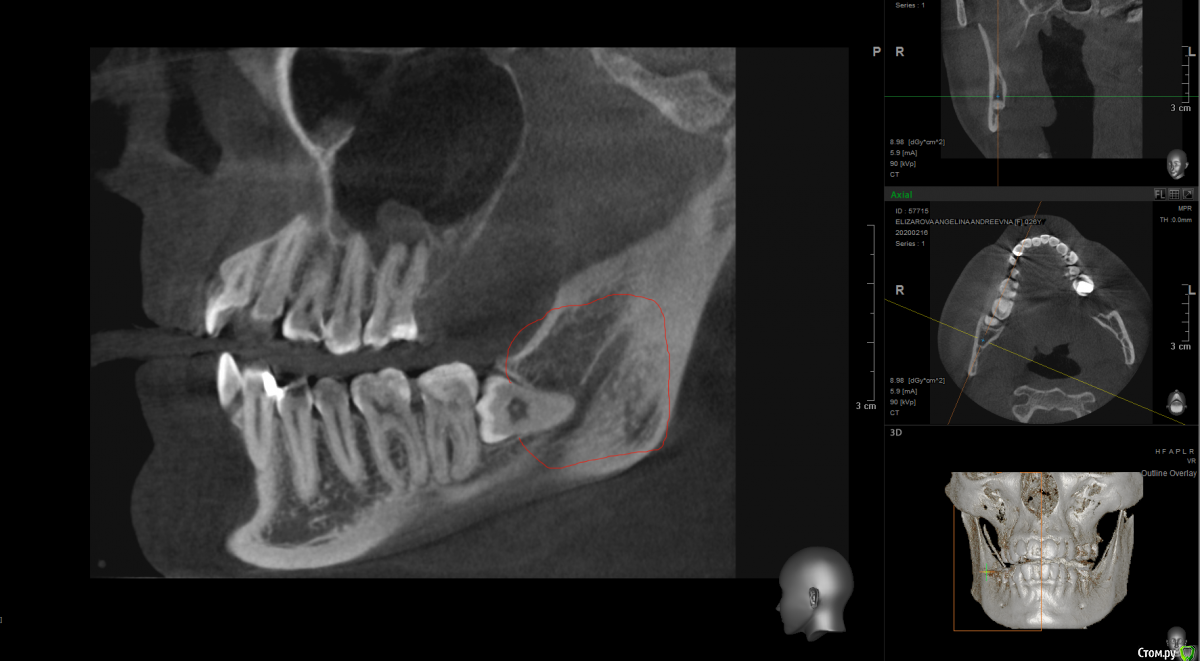

It'sGeorgy Опубликовано 17 февраля, 2020 Поделиться Опубликовано 17 февраля, 2020 Доброго времени суток! Пациентка жалуется на чувство онемения справа в области нижней челюсти. На КТ вот такая картина:Не вижу больших проблем с удалением зуба, но не могу понять есть ли новообразование в челюсти, и, если есть, каковы его размеры:или? Заранее спасибо за помощь. Ссылка на комментарий

Dr.Berger Опубликовано 18 февраля, 2020 Поделиться Опубликовано 18 февраля, 2020 Доброго времени суток! Пациентка жалуется на чувство онемения справа в области нижней челюсти. На КТ вот такая картина:Screenshot_4.pngНе вижу больших проблем с удалением зуба, но не могу понять есть ли новообразование в челюсти, и, если есть, каковы его размеры:восемь1.pngиливосемь2.png? Заранее спасибо за помощь.а что на КТ у 47 зуба? Там периодонтит!? Ссылка на комментарий

Дмитрий М Опубликовано 23 февраля, 2020 Поделиться Опубликовано 23 февраля, 2020 чувство онемения справа в области нижней челюсти возможно даже и 48 не причина! +1 кисты не вижупочему сразу решили что причина в 8-ом зубе? ментальное смотрите, проверьте все зубы, верхнюю 8-ку, определите область онемения на коже, может у пациента больше жалоб чем клиники Ссылка на комментарий